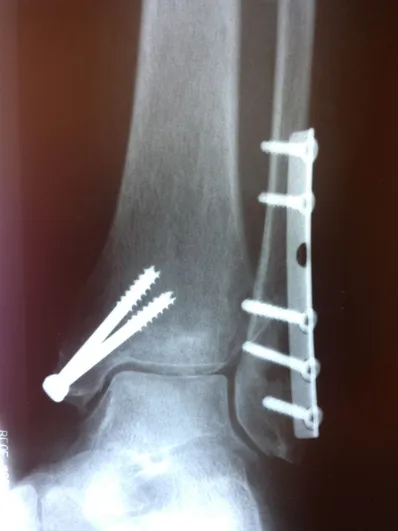

Both the lateral and medial malleolus with fractures with the lateral malleolar fracture classified as a Weber B (at the level of the ankle joint) and the medial malleolar fracture almost transverse (Left x-ray). This is indicative of a Supination External Rotation (SER IV) injury. The fractures are repaired using open reduction with internal fixation (ORIF) technique and fixated with screws and a surgical fractue plate located at the fibular (Right x-ray).

A bimalleolar fracture is a fracture of the ankle that involves the lateral malleolus and the medial malleolus. Studies have shown that bimalleolar fractures are more common in women, people over 60 years of age, and patients with existing comorbidities. Surgical treatment will often be required, usually an Open Reduction Internal Fixation (ORIF). This involves the surgical reduction or realignment of the fracture followed by the implementation of hardware to aid in the healing of the fracture. Usually a plate and screws will be used on the fibular fracture and screws, screws and pins, pins or tension band will most commonly be used on the medial malleolus fracture. A bimalleolar "equivalent" fracture is a fracture of the fibula with rupture of the superficial and deep portion of the deltoid ligaments leaving the medial malleolus intact. Surgical management is common due to the instability of the fracture and displacement of the talus laterally.

Below is the same patient seen above after surgical repair with open reduction and internal fixation with screws for the medial malleolar fracture and screws and plates for the lateral mallolar fracture. Note the even joint spacing across the ankle mortise after correction (left) that is not evenly spaced in the pre-surgical picture (above right).

Pre and Post Op X-rays of Bimalleolar Fracture Fixated with Plate and Screws